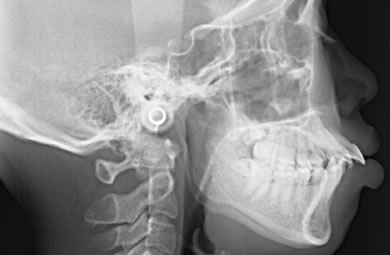

| 治療方針 | 口元が出ていていること、がたつきが大きいことより、上下左右の第一小臼歯および親知らずを抜歯し、マルチブラケット治療を行う。抜歯した隙間を活用できるよう上顎にはインプラントアンカー(釘)を使用し、その釘より歯を後ろに移動する。 | ||||||||||||||||||||||||||||||||

| 治療内容 | 唇側矯正(シルバー)、矯正用スピードインプラント、ハイブリッドセラミックインレー2本 | ||||||||||||||||||||||||||||||||